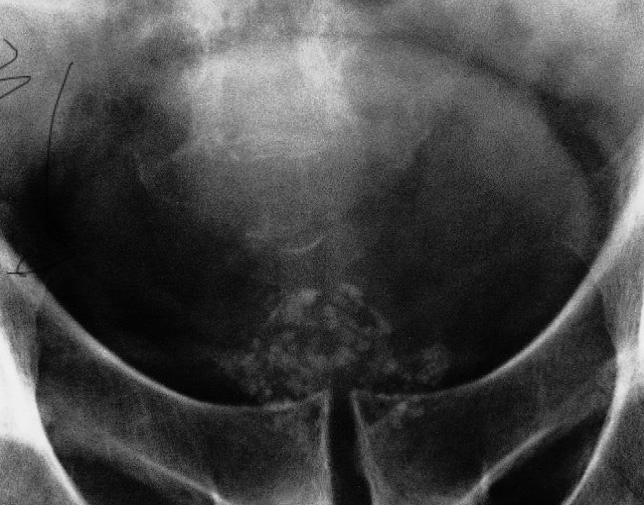

Pelvic ring fracture

X-ray pelvis (AP view)

Bilateral pubic ramus fractures are also present.